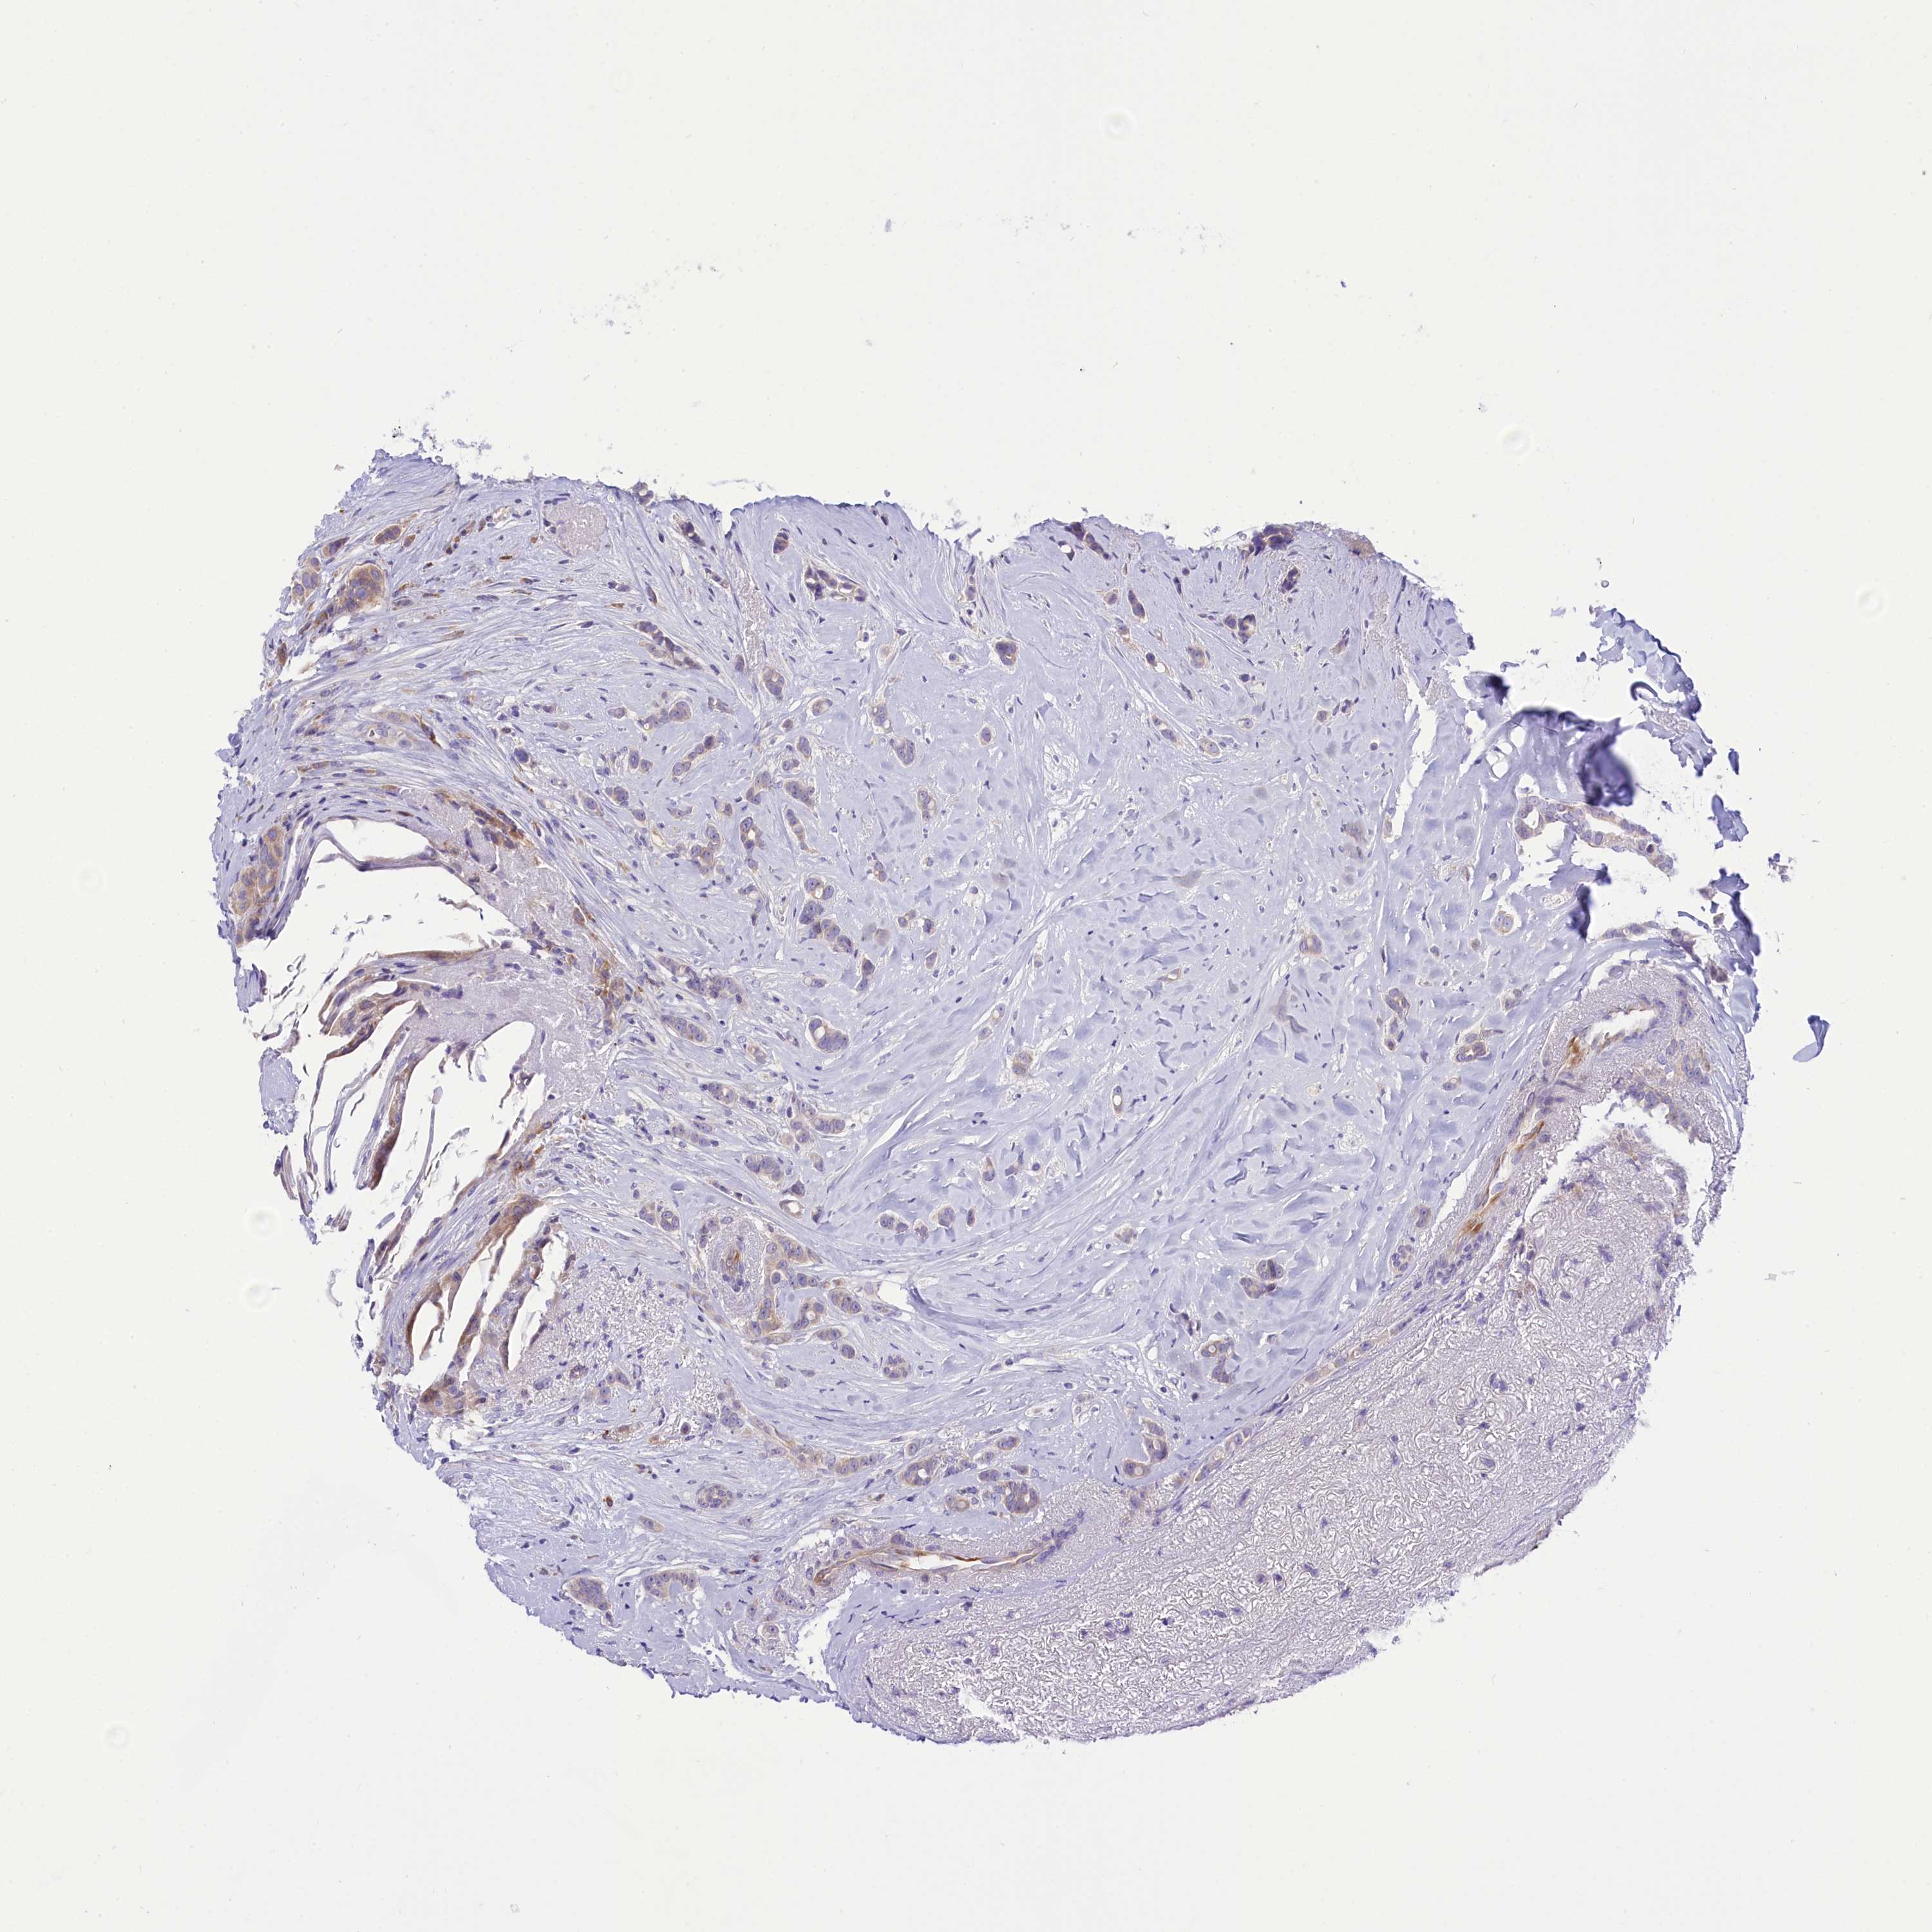

BRCA TCGA BRCA VALIDATION PROTEIN EXPRESSION